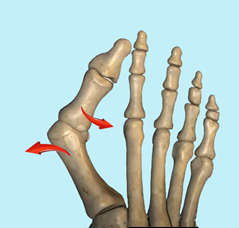

图1:拇外翻形成的机制

▶目前认为,青少年拇外翻是多因素的作用,遗传因素在本病的发生中占有更重要的作用。据报道,68%-80%的患者有家族遗传史。

▶其他如穿鞋,第1跖骨头的形态,内侧跖楔关节的倾斜和稳定性和神经肌肉疾病等都可能对拇外翻的形成有影响。